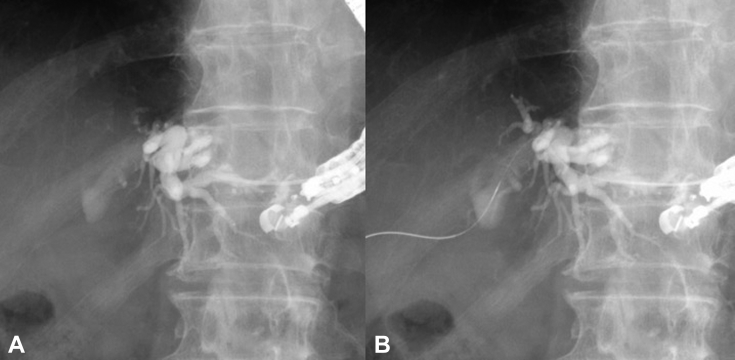

Figure 3.

A, EUS-guided hepaticogastrostomy (EUS-HGS) performed with use of a 19G needle. B, Attempt to pass an antegrade guidewire through the EUS-HGS route into the stricture of the biliojejunal anastomotic site was not possible.